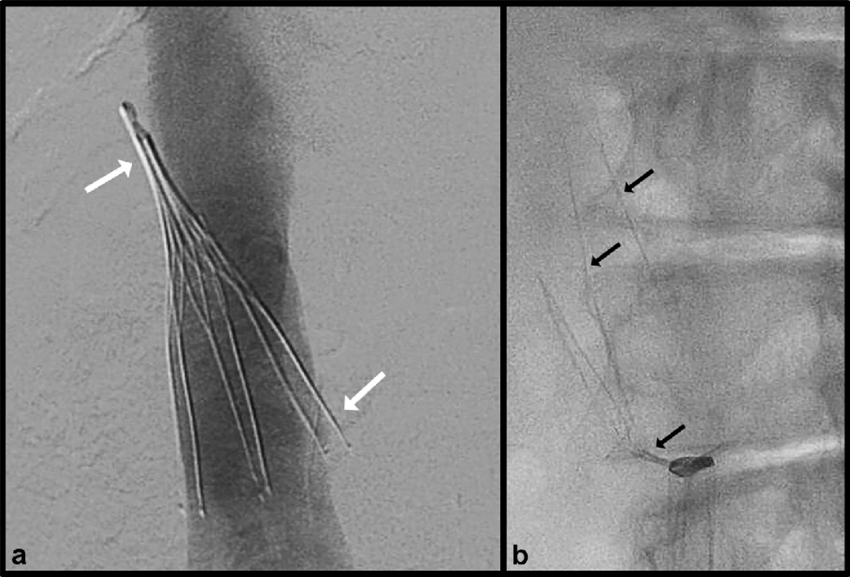

- Greenfield (Boston Scientific): مدل کلاسیک stainless steel یا titanium، معرفیشده در 1973، با پاتنسی بالا و مناسب برای IVC تا 28 mm.

• sheath (لوله بزرگتر) روی وایر پیشرفته میشود تا به موقعیت مورد نظر برسد. - باز کردن (Deployment) فیلتر ivc قلبی:

• فیلتر فشردهشده داخل sheath推進 میشود.

• sheath عقب کشیده میشود تا فیلتر باز شود و با قلابها یا پاها به دیواره IVC بچسبد.

• تکنیکهای پیشرفته مانند Over-the-Wire (OTW) برای کاهش tilt (کج شدن فیلتر) استفاده میشود.

• تصویر فلوروسکوپی برای چک موقعیت، tilt (باید کمتر از ۱۵ درجه)، migration یا perforation.

- خونریزی محل دسترسی، عفونت، malposition، tilt، migration اولیه.